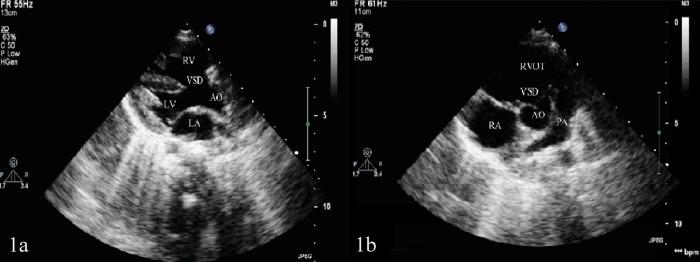

Tetralogy of Fallot is the most common cyanotic congenital heart disease. However, its pathogenesis remains to be clarified. The purpose of this study was to identify the genetic variants in Tetralogy of Fallot by whole exome sequencing.

法洛四联症是最常见的青紫型先天性心脏病。然而,其发病机制仍有待阐明。本研究的目的是通过全外显子组测序鉴定法洛四联症中的基因变异。